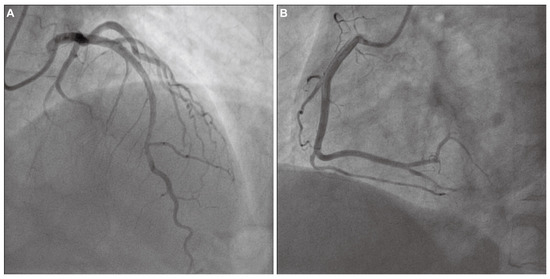

The Great Masquerader: Vasospastic Angina Mimicking Left Main Coronary Artery Disease

by Maja Wojtylak, Katarzyna Frączek, Aleksander Zeliaś and Tomasz Tokarek

J. Clin. Med. 2026, 15(5), 1952; https://doi.org/10.3390/jcm15051952 - 4 Mar 2026

A significant proportion of patients undergoing invasive coronary angiography for angina have no obstructive coronary artery disease (CAD). In such patients, coronary microvascular dysfunction (CMD) and vasospastic angina (VSA) represent key pathophysiological mechanisms. We report a case of a 58-year-old male with exertional [...] Read more.

A significant proportion of patients undergoing invasive coronary angiography for angina have no obstructive coronary artery disease (CAD). In such patients, coronary microvascular dysfunction (CMD) and vasospastic angina (VSA) represent key pathophysiological mechanisms. We report a case of a 58-year-old male with exertional chest pain and exercise ECG changes typical of left main or multivessel CAD. Coronary computed tomography angiography (CCTA) showed borderline stenosis of the distal left main coronary artery. Coronary angiography revealed no critical stenosis. A comprehensive functional assessment demonstrated reduced coronary flow reserve (CFR = 2.0) and an elevated index of microcirculatory resistance (IMR = 25), consistent with CMD. An intracoronary acetylcholine provocation test induced severe focal vasospasm of the mid-left anterior descending artery (LAD) with ST-segment elevation and anginal pain, promptly relieved by nitroglycerin, confirming VSA. This case highlights the diagnostic and clinical importance of invasive functional testing in patients with angina and non-obstructive coronary arteries (ANOCA/INOCA). The coexistence of CMD and VSA (two distinct but overlapping pathophysiological endotypes) is increasingly recognized as a marker of adverse prognosis. Functional coronary assessment should be considered in all patients with angina and non-obstructive coronary arteries, as identifying mixed endotypes enables precise, mechanism-guided therapy. Full article

(This article belongs to the Special Issue Interventional Cardiology: Recent Developments and Future Challenges)

Show Figures

Figure 1